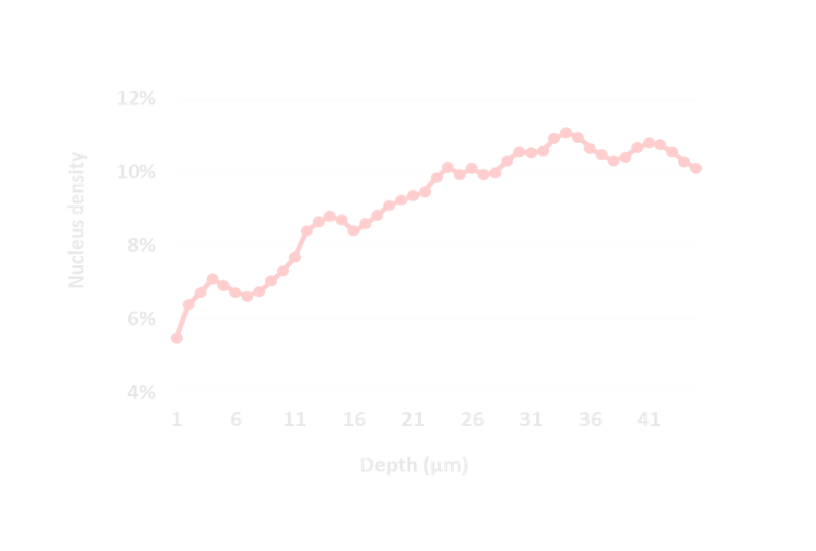

Quantitative skin analyses

adapted to your studies